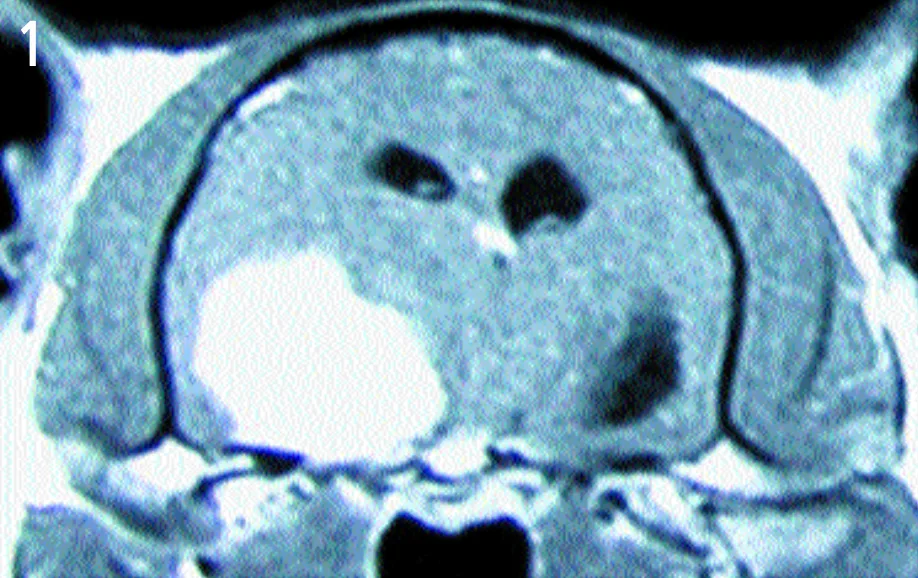

Transaxial view—T1-weighted, contrast-enhanced magnetic resonance image

A large, left-sided cerebral mass, evident on both images.

The mass is uniformly contrast-enhancing on the MRI, appears to have a broad-based attachment to the skull, and has distinct margins-all of which are characteristic of intracranial meningiomas. The most likely diagnosis is meningioma. A smaller, right-sided mass can be seen on the dorsal image. This mass also has characteristic features of meningioma. Both masses were removed and confirmed histologically as meningiomas. The cat made a full recovery.

Transaxial view—T1-weighted, contrast-enhanced magnetic resonance image